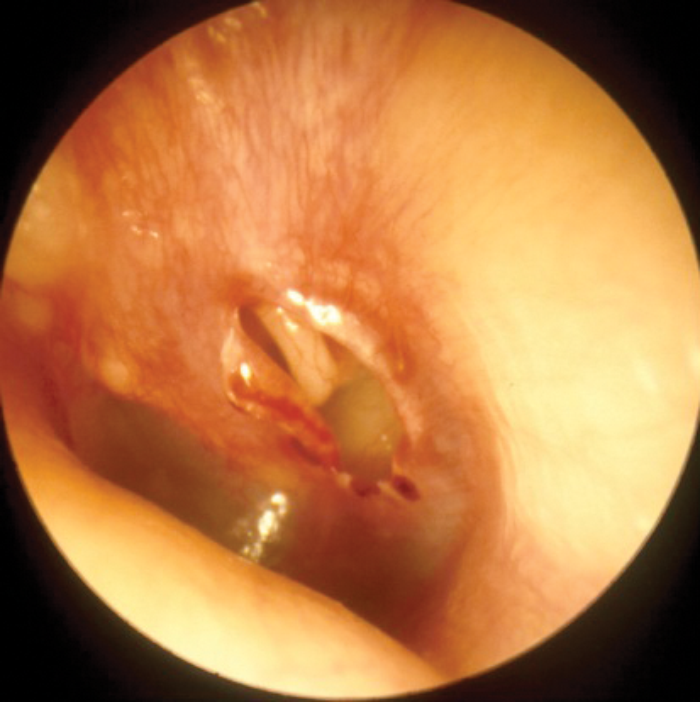

Middle ear barotrauma may be avoided by the simple solution of inserting ventilation tubes. Whilst this does not give rise to difficulty in aviators, they are contraindicated in divers because of the risk of water passing into the middle ear cavity. As already mentioned, divers may avoid middle ear barotrauma by aborting the dive, and if this is a persistent problem, the individual will be made unfit to dive. Occasionally, even an experienced diver will be required to dive rapidly, perhaps to go to the rescue of a buddy in difficulty, and this may lead to middle ear barotrauma. Grading systems exist, but the author favours a description of, ‘mild’, ‘moderate’, and ‘severe’. Initially there is hyperaemia of the tympanic membrane; followed by a middle ear effusion which may contain blood; and then perforation of the tympanic membrane. If the barotrauma has been relatively rapid, there may be little more to see than a perforation, which tends to be a tear in the tympanic membrane, rather than a hole - Figure 2.

Figure 2: Traumatic perforation.

Although tympanic perforations due to disease may be reluctant to heal, traumatic perforations usually heal rapidly - typically within two weeks. There is no hard and fast rule, but when the tympanic membrane looks normal again and the individual can demonstrate the ability to clear, flying or diving may be resumed.